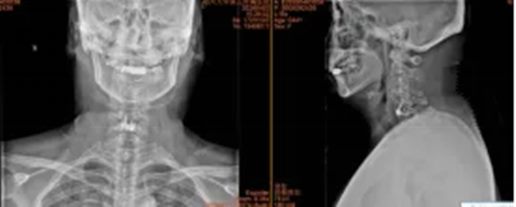

3.湖北省十堰市许先生53岁

术前:依托高分辨率CT、MRI及神经电生理监测,进行三维可视化手术规划

术中:在超声骨刀辅助下开展颈前路、颈后路或后路+前路等术式,并在神经电生理监护下确保减压彻底、置钉安全。